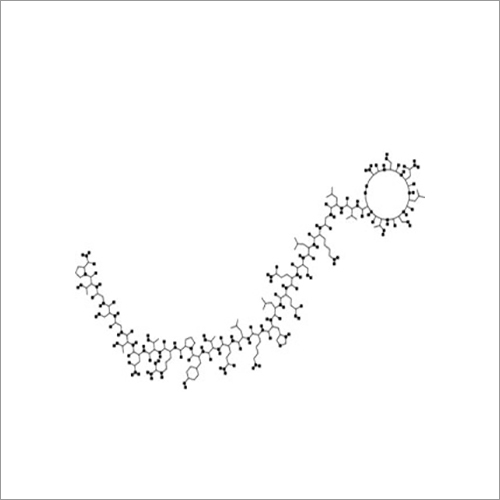

69558-55-0 थाइमोपेंटिन शुद्धता (%): > 99.0% (एचपीएलसी)

| रासायनिक नाम | Thymopentin |

| कैस नं | 69558-55-0 |

| रासायनिक नाम | Thymopentin |

| कैस नं | 69558-55-0 |